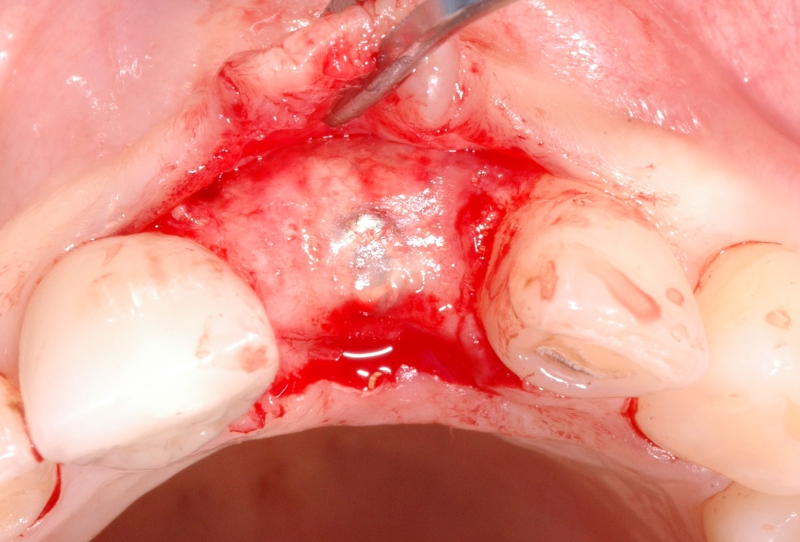

3/18 - Clinical situation 6-8 weeks after extraction, vestibular viewGBR together with soft tissue augmentation with mucoderm® and maxresorb® - Dr. S. Scherg